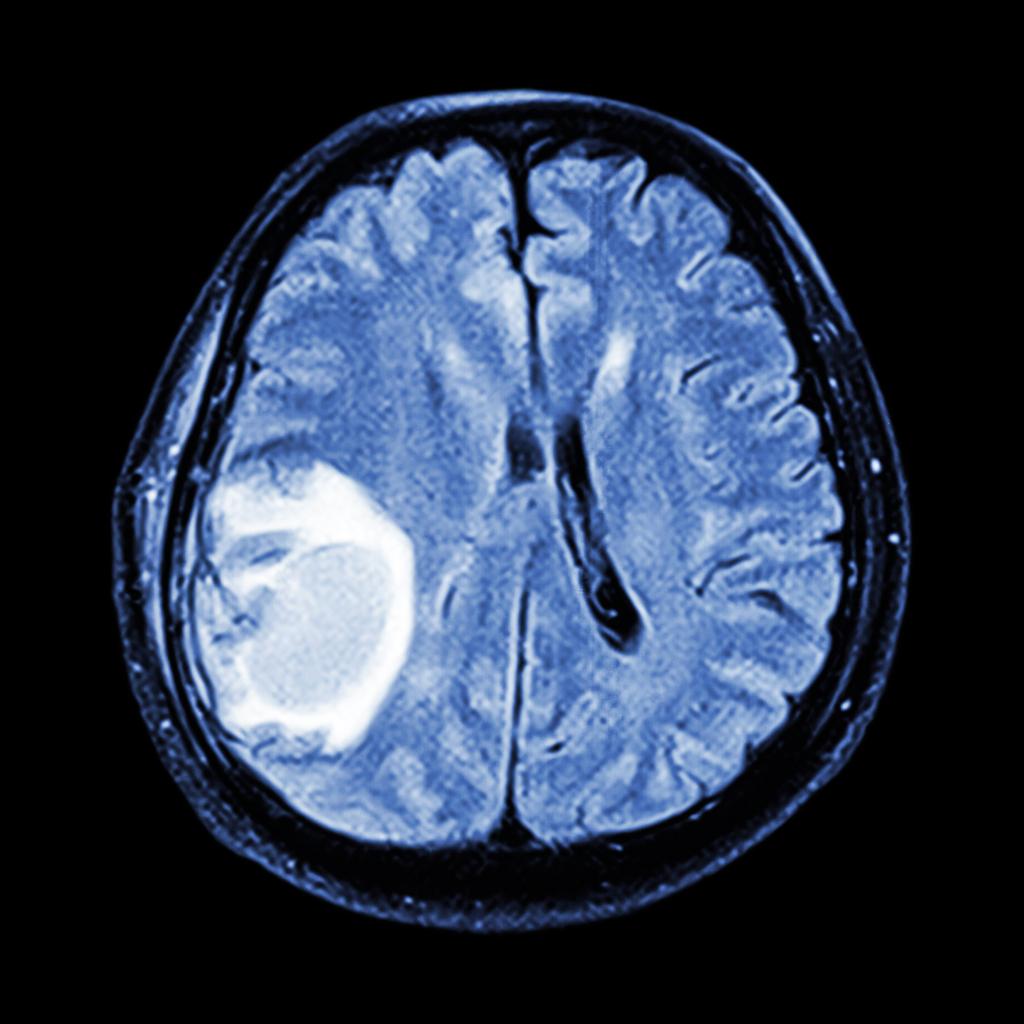

Mais en août 2018, une étude menée par l’Assurance maladie révèle que ce médicament est suspecté de multiplier jusqu'à 20 (après 5 années de traitement), et même plus, la probabilité de méningiomes, c’est-à-dire de tumeurs intracrâniennes, chez les femmes traitées longtemps et à hautes doses. Généralement bénignes, ces tumeurs peuvent occasionner de graves séquelles comme des troubles de la mémoire, de l’épilepsie ou une perte du goût et de l’odorat.

Une IRM cérébrale devra systématiquement être prescrite pour les patients débutant leur traitement, et envisagée pour la poursuite du traitement. Tant que le traitement est maintenu, l'IRM suivante interviendra au plus tard 5 ans après la première, puis tous les deux ans si l'IRM précédente est normale.